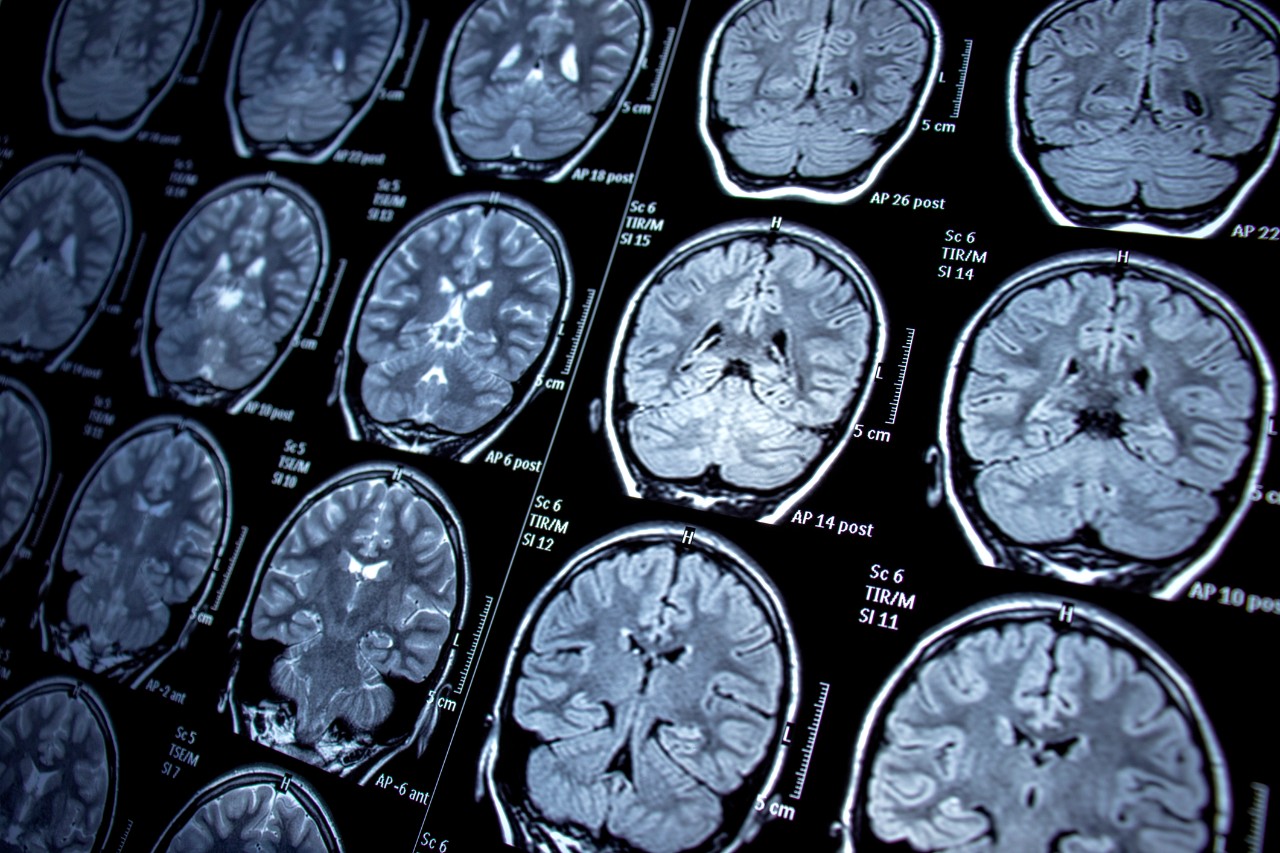

Featured photo at top of brain scans. Photo/Nur Ceren Demir/iStock.